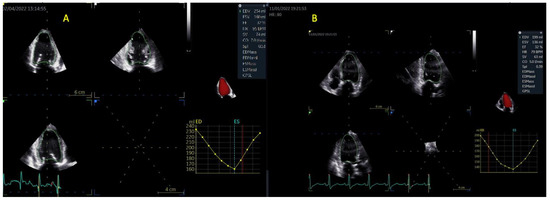

| 3D LVEDV (mL) | 214 ± 56 | 256 ± 112 | >0.05 |

| 3D LVEDV index (mL/m2) | 111 ± 32 | 135 ± 68 | 0.08 |

| 3D LVESV (mL) | 152 ± 51 | 191 ± 101 | >0.05 |

| 3D LVESV index (mL/m2) | 82 ± 25 | 96 ± 54 | 0.1 |

| 3D LVSV (mL) | 60 ± 14 | 64 ± 21 | 0.3 |

| 3D LVSV index (mL/m2) | 32 ± 7 | 31 ± 12 | 0.6 |

| 3D LVEF (%) | 31 ± 9 | 27 ± 8 | 0.1 |